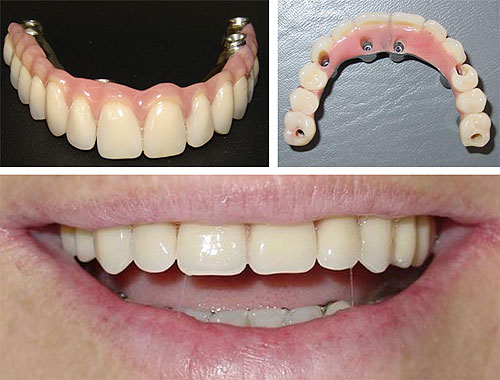

Carga Imediata

Para muitos pacientes, a necessidade de estar sem a prótese durante um período de tempo, após a instalação dos implantes, pode ser considerada inconveniência em função do convívio social e atividades profissionais. O termo carga imediata pode ser definido como instalação de implantes osseointegrados em condições ideais à estabilidade primária, seguida de ativação protética ( colocação dos dentes ) 48 horas após a cirurgia. Esta definição era aplicada à instalação de múltiplos implantes dentários e a contenção entre os mesmos promovendo um efeito de estabilidade. Com estudos recentes podemos colocar o implante unitário e colocar o dente no mesmo instante, sendo observado somente uma boa estrutura óssea.

O tratamento para colocação de implante é seguro?

O planejamento e a boa indicação de cada técnica que se utiliza é o grande diferencial do sucesso previsível. A técnica de carga imediata sem dúvida é uma ótima indicação para situações em que a quantidade e qualidade ósseas e os hábitos oclusais sejam favoráveis a sua aplicação.

Quanto tempo leva para ser feito ?

O processo leva cerca de 2 ou 3 dias variando de acordo com o número de dentes a serem implantados no paciente. Em reabilitações totais, na média, são realizados 6 a 8 implantes para cada arcada ( superior ou inferior ) em uma única sessão cirúrgica. Com o modelo em mãos é confeccionada a infra-estrutura que é provada em uma sessão, normalmente no dia seguinte a cirurgia. A infra-estrutura volta ao laboratório onde recebe os dentes. Depois a peça pronta é colocada.

A utilização de implantes unitários com procedimentos de carga imediata é discutível, porém em situações isoladas, nos quais fatores clínicos e gerais do paciente favorecem tal indicação, há possibilidade da instalação de elementos unitários, com o acompanhamento periódico regular , durante e após o processo de osseointegração, realizado também nos demais casos.

Podemos prever o resultado ?

Observando o estudo comparativo entre a técnica convencional estabelecida por BRANEMARK e o protocolo de carga imediata temos como grandes vantagens a diminuição do tempo das consultas e a rapidez dos resultados oferecidos ao paciente, com efeito psicológico e social melhorados, já que os resultados geram bem estar funcional e estético. Os pacientes devem ser selecionados e a indicação estabelecida após controle sistêmico da saúde e das condições locais favorecidas para essa técnica. Comparada com a técnica convencional onde o paciente esperaria normalmente de 3 a 6 meses para a colocação dos dentes, a técnica da carga imediata pode ser uma ótima opção.